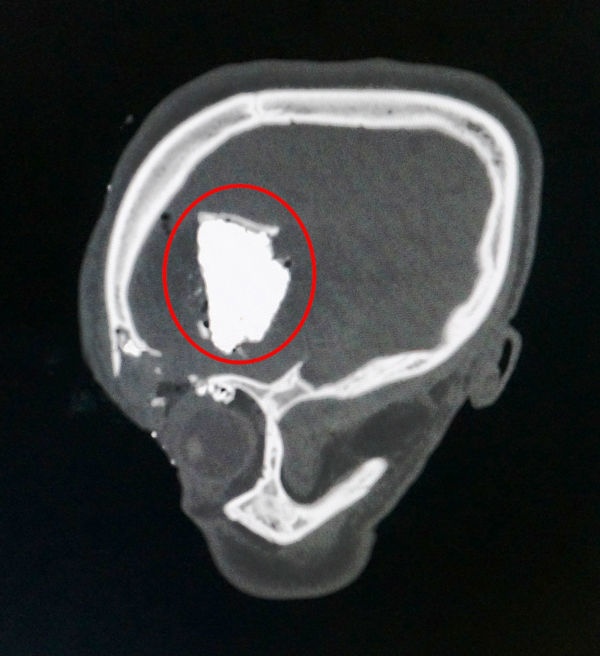

Ổ giun đũa chó mèo tấn công lên não khiến anh Dinh bị chẩn đoán nhầm mắc một loại u hiếm gặp.